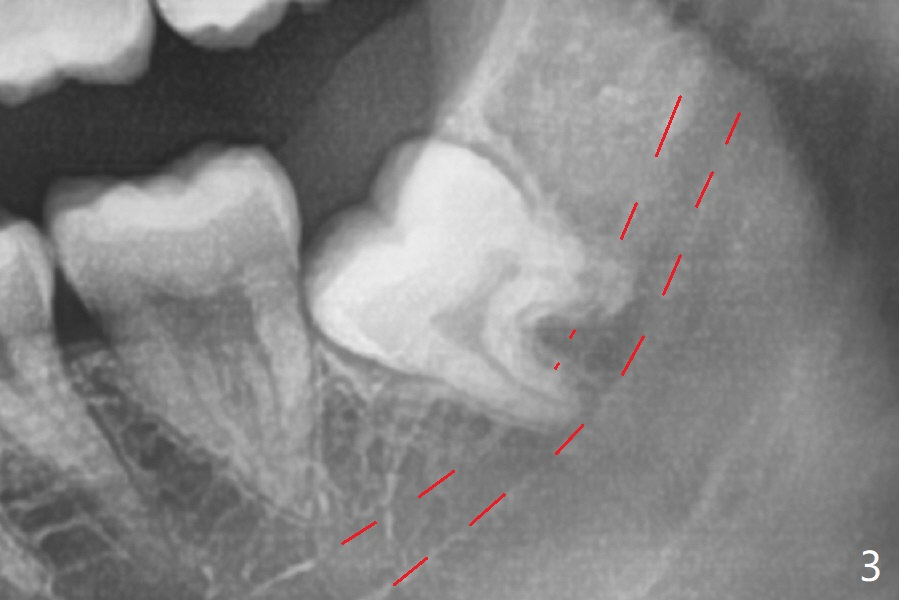

A 17-year-old man will return for extraction of 4 of the 3rd molars (Fig.1). Since the distobuccal surface of the tooth #31 may lack the bone (Fig.2 *), half of Augma will be placed in the distal portion of the sockets of #17 and 32, while allograft in the mesial one. Take PAs immediately post extraction to determine bony defects of the lower 3rd molars. Insert a piece of 2x2 gauze into the socket immediately post extraction. If hemorrhage is severe because of closeness between the mesial roots of the lower 3rd molars and the Inferior Alveolar Canal (Fig.2,3 red dashed line) after removal of the gauze, insert a half piece of Collagen Plug or more into the socket. If the latter is effective in hemostasis, Augma will be not applied, but allograft will be used, followed by Collagen Plug on the top of the allograft and sutures. Prepare both 4-0 and 5-0 ones. In fact the patient chooses to have 2 of the 3rd molars to be extracted. The extraction at #32 turns out to be extremely difficult with numerous sectioning because the crown of #32 is embedded into the distolingual surface of the fused conical roots of #31 (Fig.4,5). After insertion of a whole piece of Osteogen plug (Fig.7 O) into the root portion of the socket, Bond Apatite (1 cc) is pressed into the coronal portion of the socket (Fig.6 A). Due to oozing, the cement does not seem to be set completely. One third piece of Collagen plug is placed on the top of the cement before 4-0 Chromic gut suturing tightly. CBCT will be taken for better treatment approach prior to #17 extraction. Return to Plug Augma Xin Wei, DDS, PhD, MS 1st edition 10/06/2019, last revision 12/28/2019